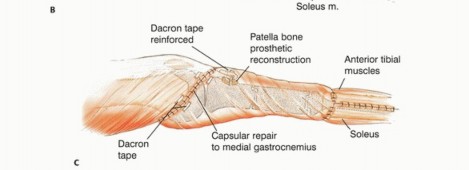

آلية المد

يتم استئصال موقع ارتباط آلية المد (الوتر الرضفي عند حديبة قصبة الساق) بشكل كتلة واحدة مع قصبة الساق القريبة. إعادة بناء هذه الآلية أمر ضروري لوظيفة الطرف المصاب. بدون إعادة بناء فعالة، قد يعاني المريض من ضعف كبير في القدرة على مد الركبة، مما يؤثر على المشي والحركة.

دور سديلة العضلة التوأمية الإنسية (Gastrocnemius Rotational Flap)

يُعد استخدام سديلة العضلة التوأمية الإنسية (عضلة الساق) عاملاً رئيسياً في تحقيق تغطية كافية للأنسجة الرخوة للطرف الصناعي واستعادة وظيفة آلية المد. تُنقل هذه العضلة لتدور إلى الأمام لتغطية الطرف الصناعي، مما يقلل بشكل كبير من خطر العدوى ومضاعفات الجروح، وهو ما كان يمثل تحدياً كبيراً في الماضي. يؤكد الأستاذ الدكتور محمد هطيف على أن هذه التقنية أصبحت إجراءً روتينياً وموثوقاً لضمان تغطية الطرف الصناعي وتقليل معدل العدوى ونخر السديلة والبتر الثانوي.

تفاصيل الإجراء الجراحي للحفاظ على الطرف

تُعد جراحة الحفاظ على الطرف في أورام قصبة الساق القريبة إجراءً معقداً يتطلب خبرة جراحية عالية وتخطيطاً دقيقاً. يقوم الأستاذ الدكتور محمد هطيف بتطبيق أحدث التقنيات لضمان استئصال الورم بشكل كامل وإعادة بناء الطرف بأمان وفعالية. تتضمن الجراحة ثلاث خطوات رئيسية:

- استئصال الورم: إزالة الجزء المصاب من قصبة الساق والأنسجة المحيطة به مع هامش أمان كافٍ.

- إعادة بناء العيب الهيكلي ومفصل الركبة: زرع طرف صناعي أو طعم عظمي لاستبدال الجزء المستأصل.

- إعادة بناء آلية المد وتغطية الطرف الصناعي بالأنسجة الرخوة: استخدام سديلة العضلة التوأمية لضمان التغطية والحفاظ على وظيفة الركبة.